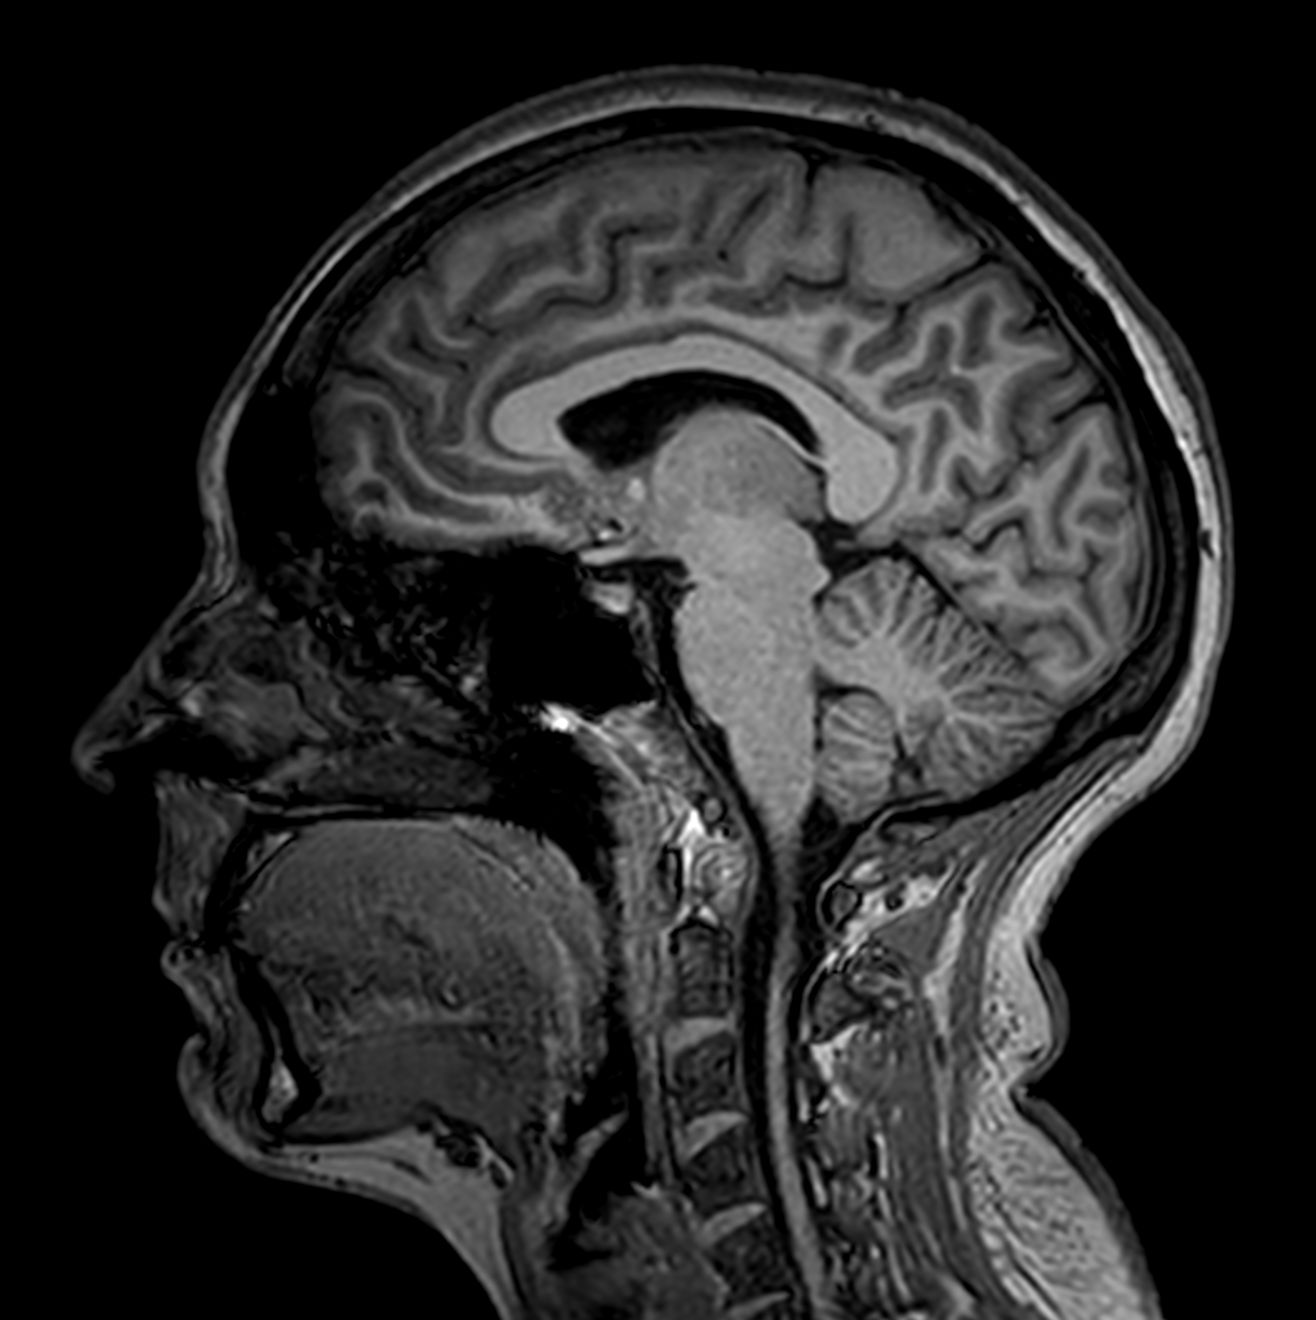

Alzheimer’s Disease Anti-Amyloid Immunotherapies (ARIA) 3.0T

Amyloid clearing medication, such as Aduhelm (Aducanumab) and Leqembi (Lecanemab) have been cleared by the FDA in 2022/2023, to slow down cognitive decline in early-stage Alzheimer’s disease. ASNR-recommendations for AD therapeutic imaging were published in 2022 for eligibility assessment as well as for monitoring for amyloid-related imaging abnormalities. This ExamCard includes ASNR-recommended consensus protocols for imaging of Alzheimer’s Disease Anti-Amyloid Immunotherapies (ARIA). (Cogswell et al., AJNR 2022,43(9)E19-E35;DOI: https://doi.org/10.3174/ajnr.A7586))